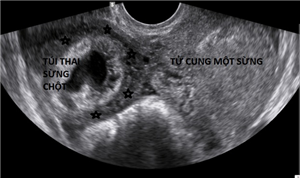

CLS: Thai ở sừng chột tử cung